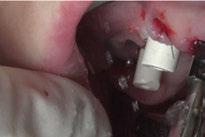

Para ilustrar el proceso, presentamos el caso de una mujer joven diagnosticada de carcinoma adenoide quístico en la región posterior del hemipaladar izquierdo (Figuras 1 y 2). El procedimiento quirúrgico realizado fue una

maxilectomía parcial que incluyó las piezas 24-26 y desde el reborde alveolar hasta la base del cráneo (Figuras 3 y 4). En este caso, la órbita y el globo ocular pudieron ser preservados. La reconstrucción inmediata se realizó mediante un colgajo de músculo temporal homolateral (Figura 5) y el defecto de la fosa temporal fue cubierto mediante una malla de titanio. Posteriormente, la paciente recibió radioterapia (Figuras 6 y 7). 2 años más tarde se diseñó un IS con anclaje en el arbotante nasomaxilar, zona subnasal izquierda

Figura 3. Maxilectomía parcial.